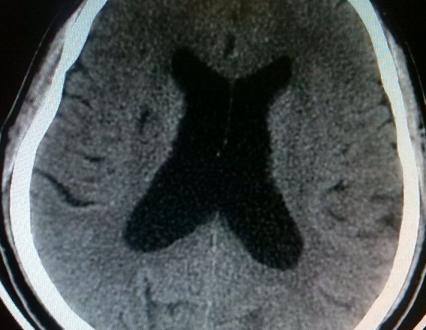

脑梗塞后遗症这是常见的脑血管病,它多发于老年人,复发率非常高。恢复期治疗目的就是改善头晕头痛、肢体麻木障碍、语言不利等症状的,使之达到最佳的一个态势;同时降低脑梗塞后遗症的高复发率。接下来就为大家详细的介绍一下。

脑梗塞后遗症属于高复发不可逆性的慢性脑血管意外,病人出院后仍需按医生嘱咐规律服药,控制好高血压、高血脂、糖尿病等动脉硬化的基础病变,并定期到医院复查。常用治疗脑梗塞后遗症的有效药物包括抗血小板聚集类药物,如拜阿司匹林;脑保护营养药物,益气活血开窍止痛药物。